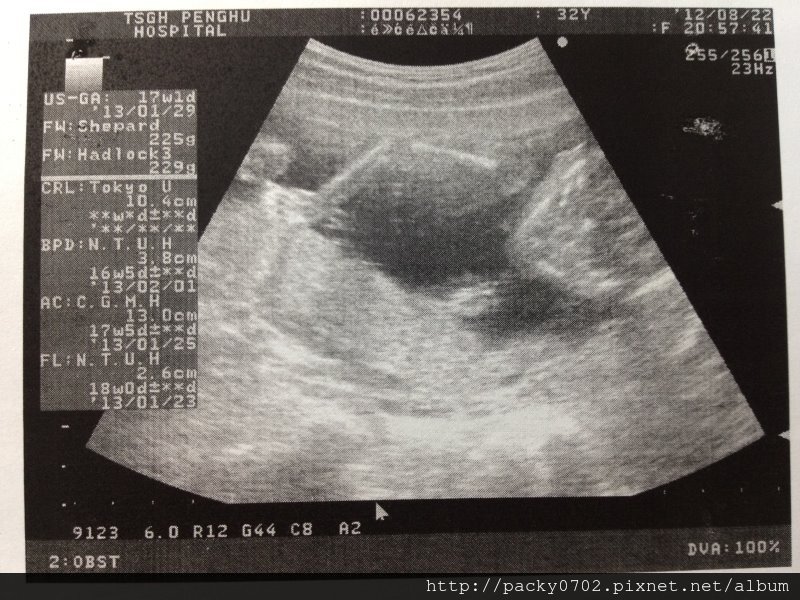

這時候小寶寶全長是10.4cm,但之後其實就不會量身長了~

20120822 (3)

這時候小寶寶頭圍是3.8cm,正常size

20120822 (4)

上頭那長長的就是他的大腿骨啦,聽說遺傳了媽媽的長腿喔~

20120822 (5)

寶寶:身長10.4cm,頭圍3.8cm,肚圍13.0cm,大腿骨長2.6cm,重量225g